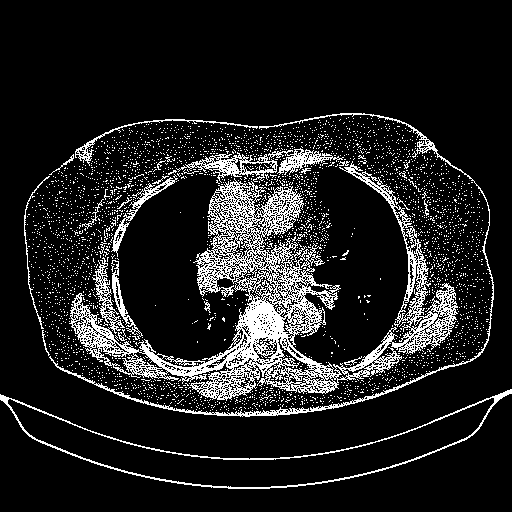

Generated VENOUS CT scan (A→B translation)

Full window (WL 1023.5, WW 4095 β†’ Low βˆ’1024, High +3071)

Actual HU range: [-1024.0, 3071.0]